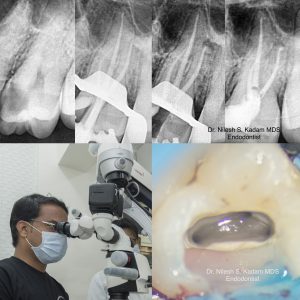

Root canal treatment involves removing the infected or damaged pulp, which is the soft inner part of the tooth, and then thoroughly cleaning and disinfecting the interior of the tooth. Once the tooth is cleaned, it’s sealed with a special material to prevent further infection. Contrary to popular belief, the procedure is typically no more uncomfortable than getting a standard dental filling.

Following a successful root canal, your dentist can place a crown on the treated tooth. This crown not only strengthens the tooth but also improves its appearance, ensuring that your smile looks as good as it feels.